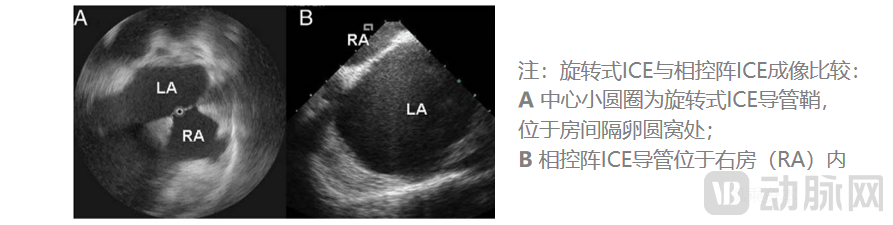

ICE使用5~12MHz的超声频率,理论最高分辨率可以达到0.1mm、且同时具有最高16cm的心内穿透成像深度。常见的2D ICE导管分为单阵元旋转超声导管、电子相控阵列超声导管两类,目前后者在临床上更为常用。目前ICE导管直径为8~10Fr。

就2D ICE来说,相控阵ICE相比单阵元旋转ICE具有以下优势:更深成像深度、获取多普勒血流彩超的能力。相控阵ICE因而在2D ICE当中更受青睐。